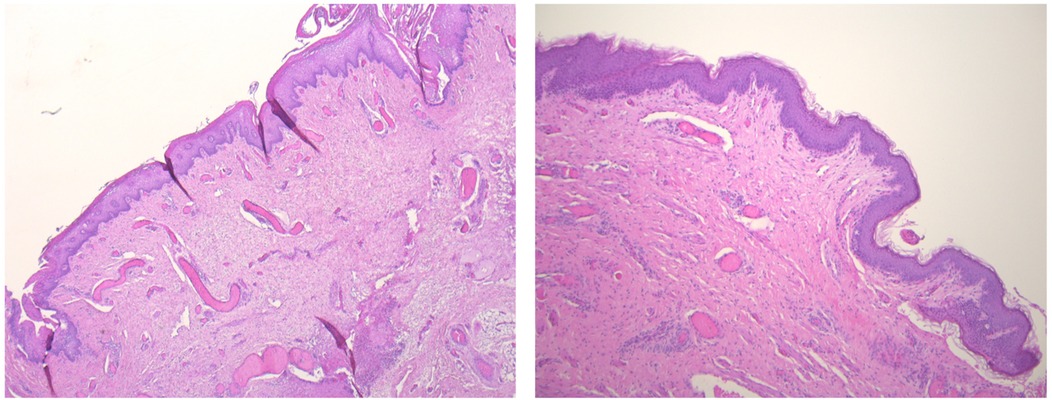

Postoperative histopathological analysis of the excised tissue confirmed the diagnosis of a CMCC, with no evidence of fistulous structures or ectopic salivary gland tissue. These findings were critical in excluding other differential diagnoses and solidifying the classification of the anomaly (Figure 4).

Microscopic images of skin tissue sections. The left panel shows a wavy pattern of dermal papillae, while the right panel displays a thicker, more uniform epidermis. Both images are stained with hematoxylin and eosin, highlighting cellular structures in shades of pink and purple.

Figure 4. Histopathological features of the CMCC. Hematoxylin and eosin staining (40× magnification) reveals a cleft lined by stratified squamous epithelium with surface parakeratosis. The underlying dermis lacks adnexal structures but contains abundant striated muscle bundles at deeper levels. Similarly, the cephalic papule is composed of a stratified squamous epithelial lining overlying muscle bundles, which progressively transition into normal skin with adnexal structures, highlighting the lesion's interaction with surrounding tissue.